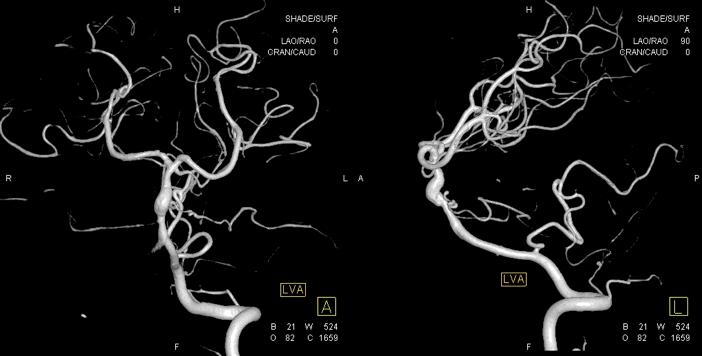

本院 DSA三维血管重建(2019-10-10)显示:基底动脉巨大夹层动脉瘤(图7)。

图7

治疗过程简述

1、患者全身麻醉,右侧股动脉穿刺置入8F动脉鞘,5F中间导管携带6F长鞘超选入左侧椎动脉,行造影及三维旋转寻找最佳工作角度(图8)。

图8